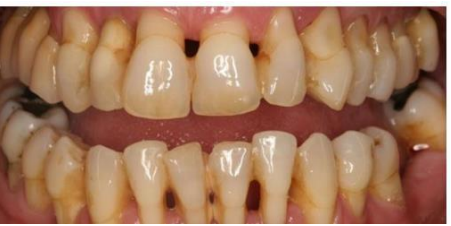

MFD EXAMS /23 6 1234567891011121314151617181920212223 You have 30 min to complete this exam. The timer will start once you begin Attention: Only a few minutes left! Please submit your answers soon. MFD 1 Get a quick sneak peek before the real exam !This trial quiz is designed to show you the question style, difficulty level, and how the options will appear on the platform. 1 / 23 1. What is the lethal dose and toxic dose of fluoride, management? Check 2 / 23 2. What the advantage of silver diamine over other methods and disadvantages ? Check 3 / 23 3. Method of topical fluoride application with concentration ? Check 4 / 23 4. What will happen if left untreated? Check 5 / 23 5. What changes that will happen if the habit stopped? Check 6 / 23 6. Give 3 of your initial stage of treatment? Check 7 / 23 7. What are the causes? Check 8 / 23 8. What is this? Check 9 / 23 9. Then they specified the type of pain and asked about the diagnosis Check 10 / 23 10. What other tests to check vitality of the pulp? Check 11 / 23 11. What are the factors will govern the Rx of Posterior cross bite ? Check 12 / 23 12. What are the factors that govern the treatment of anterior cross bite? Check 13 / 23 13. Name the appliance that you can use to treat this case? Check 14 / 23 14. Name 3 causes? Check 15 / 23 15. Name the most important clinical diagnostic information you need to know. (check RCSI intensive course )? Check 16 / 23 16. What do you see? Check 17 / 23 17. What is your treatment? Check 18 / 23 18. Name the investigations needed? Check 19 / 23 19. causes for gingival enlargement ? Check 20 / 23 20. What is the common side effect of this drug? Check 21 / 23 21. Name the drug that he may take to treat this condition? Check 22 / 23 22. The patient may have what? Check 23 / 23 23. What is this clinical condition? Check /31 2 12345678910111213141516171819202122232425262728293031 You have 30 min to complete this exam. The timer will start once you begin Attention: Only a few minutes left! Please submit your answers soon. MFD 2 Get a quick sneak peek before the real exam !This trial quiz is designed to show you the question style, difficulty level, and how the options will appear on the platform. 1 / 31 1. Mention 2 fixed space maintainers and 2 removable space maintainers other from mentioned : Check 2 / 31 2. Other space maintenance used for child lost primary second molar E before the eruption of the permanent molars ? Check 3 / 31 3. What are the difference between nance appliance and Transpalatal arch Check 4 / 31 4. What material used to attach band? Check 5 / 31 5. What instruction you give to patient? Check 6 / 31 6. Name other fixed space maintainer used in upper jaw and mechanism of their action? Check 7 / 31 7. What component of this appliance? Check 8 / 31 8. What is this appliance , for what its used ? Check 9 / 31 9. Treatment? Check 10 / 31 10. Define Abrasion and Erosion? Check 11 / 31 11. What does this picture show? Check 12 / 31 12. what investigations you can do ? Check 13 / 31 13. Drugs can lead to lichenoid reaction Check 14 / 31 14. What extra oral features in “ Lichenoid reaction )? Check 15 / 31 15. What microscopical features of it ( licheonoid reaction )? Check 16 / 31 16. Definitive diagnosis ? Check 17 / 31 17. Mention type of suggested biopsy ? Check 18 / 31 18. Mention 4 differential diagnosis ? Check 19 / 31 19. Mention 4 questions you will ask the patient ? Check 20 / 31 20. Give 4 intraoral decription of what you see ? Check 21 / 31 21. What the other surgery can be performed to make prothesis? Check 22 / 31 22. Can this tooth stand with fixed prothesis? (in the opg )à taken from Malek file ? Check 23 / 31 23. Radiograph of missing multiple teeth consider it according to Antes law? ON which tooth you will make Abutment ? Check 24 / 31 24. What is Antes law? Check 25 / 31 25. What is best one to use as abutment in fixed prosthesis A or B? Check 26 / 31 26. What relevance of this picture? Check 27 / 31 27. What’s complication of doing surgery in this area floor of mouth? Check 28 / 31 28. Other 2 radiograph needed in diagnosis? Check 29 / 31 29. Give 4 differential diagnosis? Check 30 / 31 30. What can you see ? Check 31 / 31 31. What is the name of radiograph? Check Your score is /30 1 123456789101112131415161718192021222324252627282930 You have 30 min to complete this exam. The timer will start once you begin Attention: Only a few minutes left! Please submit your answers soon. MFD 3 Get a quick sneak peek before the real exam !This trial quiz is designed to show you the question style, difficulty level, and how the options will appear on the platform. 1 / 30 1. Treatment? Check 2 / 30 2. Histopathology? Check 3 / 30 3. Differential diagnosis Check 4 / 30 4. Clinical features’? Check 5 / 30 5. Patient said, this lesion is very frequent, why? Check 6 / 30 6. What are the causes for ulcers? Check 7 / 30 7. Patient have other signs like uveitis ,Genital ulcerations which syndrome he had ? Check 8 / 30 8. Name of the lesion ? Check 9 / 30 9. Mention some TMJ movement ? Check 10 / 30 10. Blood supply ? Check 11 / 30 11. Nerve supply ? Check 12 / 30 12. Which muscles close? Check 13 / 30 13. Action of open and open wide? Check 14 / 30 14. Why it’s Atypical joint ? Check 15 / 30 15. Name of the ligaments ? Check 16 / 30 16. What would be your management? Check 17 / 30 17. Bacteria involved Check 18 / 30 18. Which type of Periodontitis? Check 19 / 30 19. Treatment? Check 20 / 30 20. Histopathology? Check 21 / 30 21. Differential diagnosis? Check 22 / 30 22. Clinical features? Check 23 / 30 23. What are the time frames for making a complaint? Check 24 / 30 24. What are the 3 points related to negligence? Check 25 / 30 25. Who is allowed access to the patient records? Check 26 / 30 26. How to differentiate if it is upper or lower motor neuron lesion? Check 27 / 30 27. Management? Check 28 / 30 28. What are the causes? Check 29 / 30 29. What should you advise the patient to do? Check 30 / 30 30. What is this lesion? Check Your score is /24 1 123456789101112131415161718192021222324 You have 30 min to complete this exam. The timer will start once you begin Attention: Only a few minutes left! Please submit your answers soon. MFD 4 Get a quick sneak peek before the real exam !This trial quiz is designed to show you the question style, difficulty level, and how the options will appear on the platform. 1 / 24 1. What does MRONJ stands for? Check 2 / 24 2. Give definition for MRONJ Check 3 / 24 3. For what medical problems these medications are used? Check 4 / 24 4. Stages of MRONJ 3 Check 5 / 24 5. What’s this appliance? Check 6 / 24 6. At what age is it used? Check 7 / 24 7. What type of malocclusion is it used to treat? Check 8 / 24 8. What changes will produce? (4 options) Check 9 / 24 9. Disadvantages? Check 10 / 24 10. Why is it flabby tissue? Check 11 / 24 11. what is this condition called? Check 12 / 24 12. Causes ? Check 13 / 24 13. Clinical Features ? Check 14 / 24 14. How to avoid it ? Check 15 / 24 15. Management? Check 16 / 24 16. Ideal post length and width Check 17 / 24 17. Definition of Ferrule it’s the Check 18 / 24 18. What is the importance of the ferrule effect ? Check 19 / 24 19. Describe the radiolucency? Check 20 / 24 20. Give 6 differential diagnosis? Check 21 / 24 21. Give 5 radiographical features? Check 22 / 24 22. What is the difference between incisional and excisional biopsy? Check 23 / 24 23. What other 2 plain radiographs we can we can take? Check 24 / 24 24. ALARA? Check Your score is /22 1 12345678910111213141516171819202122 You have 30 min to complete this exam. The timer will start once you begin Attention: Only a few minutes left! Please submit your answers soon. MFD 5 Get a quick sneak peek before the real exam !This trial quiz is designed to show you the question style, difficulty level, and how the options will appear on the platform. 1 / 22 1. . Types of external root resorption? Check 2 / 22 2. The cause of root resorption in the pic? Check 3 / 22 3. How you will treat it? Check 4 / 22 4. What is this probe? Check 5 / 22 5. What is the mark a ? Check 6 / 22 6. What is the mark b ? Check 7 / 22 7. What is the score from the given reading? Check 8 / 22 8. What is the treatment need of the patient according to the score? Check 9 / 22 9. What is the differential diagnosis ? Check 10 / 22 10. Four clinical features of the lesion? Check 11 / 22 11. Treatment ? Check 12 / 22 12. Describe what do you see? Check 13 / 22 13. Causes for it ? Check 14 / 22 14. Treatment ? Check 15 / 22 15. Picture of patient with Anaphylaxis…after taking Check 16 / 22 16. What is diagnosis? - Check 17 / 22 17. What a the signs of Anaphyalxis reactions ? Check 18 / 22 18. What first line of treatment? Dose? Route of Adminstration? Check 19 / 22 19. Other drug used? Check 20 / 22 20. What are expected complications if not treated ? Check 21 / 22 21. What precautions should be made to prevent anaphylaxis reaction ? - Check 22 / 22 22. Name 10 drug in emergency used with their route of Administration and their condition they use in? Check Your score is /36 1 123456789101112131415161718192021222324252627282930313233343536 You have 30 min to complete this exam. The timer will start once you begin Attention: Only a few minutes left! Please submit your answers soon. MFD 6 Get a quick sneak peek before the real exam !This trial quiz is designed to show you the question style, difficulty level, and how the options will appear on the platform. 1 / 36 1. . What are cases that you have to extract the primary tooth? Check 2 / 36 2. D. What are the indications for extraction? Check 3 / 36 3. What are your treatment options? Check 4 / 36 4. Investigations? Check 5 / 36 5. Type of trauma? Check 6 / 36 6. Patient diagnosed with sjorgen syndrome Histology ? - Check 7 / 36 7. Patient diagnosed with sjorgen syndrome Mention four blood investigations ? Check 8 / 36 8. Patient diagnosed with sjorgen syndrome Mention two sites where can we take the biopsy Check 9 / 36 9. Patient diagnosed with sjorgen syndrome How can you differentiate between primary and secondary ? Check 10 / 36 10. Gingival inflammation present in which syndrome Check 11 / 36 11. What is the treatment? Check 12 / 36 12. mention another connective tissue disease that can lead to lesions “ intraorally “ similar to the Lichen planus ? Check 13 / 36 13. what serious complication can arise from Erosive lichen planus ? Check 14 / 36 14. If it was atrophic lesion what histology might be seen ? Check 15 / 36 15. List the histological features of lichen planus ? Check 16 / 36 16. Lichen planus what dose it affect? Check 17 / 36 17. Age group commonly affected ? -ref SAQ Check 18 / 36 18. What are the clinical presentation ‘ types of lichen planus ‘ Check 19 / 36 19. What might you see in patient’s body that has a relation to this lesion? Check 20 / 36 20. What are the differential diagnoses? Check 21 / 36 21. Factors for platelet adhesion? Check 22 / 36 22. What can you see? Check 23 / 36 23. Other 2 process of hemostasis? Check 24 / 36 24. Two diseases in which they increase ? Check 25 / 36 25. Two diseases in which they decrease? Check 26 / 36 26. Medical term when they decrease? And if they increased Check 27 / 36 27. Function Check 28 / 36 28. Life span ? Check 29 / 36 29. From where they arise? Check 30 / 36 30. Normal number? Check 31 / 36 31. What are the function of the guiding plane ? Check 32 / 36 32. The success rate ? Check 33 / 36 33. Mention single extra preparation requirement for Resin bonded bridge in posterior teeth ? Check 34 / 36 34. Mention 5 preparation features of it? Check 35 / 36 35. Give two advantages of it ? Check 36 / 36 36. What’s the name of this prosthesis? Check Your score is /23 1 1234567891011121314151617181920212223 You have 30 min to complete this exam. The timer will start once you begin Attention: Only a few minutes left! Please submit your answers soon. MFD 7 Get a quick sneak peek before the real exam !This trial quiz is designed to show you the question style, difficulty level, and how the options will appear on the platform. 1 / 23 1. If the same scenario but the tooth is subluxated. What is the management? Check 2 / 23 2. Aim of this procedure Check 3 / 23 3. Steps to do this procedure? Check 4 / 23 4. Management? How to asses the vitality of the tooth Check 5 / 23 5. Mention factors that can affect the treatment plan ? Check 6 / 23 6. Identify the Kenneyd’s classification Check 7 / 23 7. Name its parts? Check 8 / 23 8. Uses of Surveyor Check 9 / 23 9. What is this ? Check 10 / 23 10. Criteria for hand piece sterilization Check 11 / 23 11. steps for wrapped instrument sterilization process ( ref : sterilization in SDCEP)? Check 12 / 23 12. What is the difference between sterilization and decontamination? Check 13 / 23 13. Optimal temperature & pressure & time for autoclave? Check 14 / 23 14. Difference between vacuum and non-vacuum autoclave in mechanism? Check 15 / 23 15. Optimum temperature? Check 16 / 23 16. Advantage of vaccum over non vaccum? Check 17 / 23 17. What is the significance of forehead wrinkling? Check 18 / 23 18. What is Ramsy haunt syndrome ? Rx ? and is it LMN or UMN ? Check 19 / 23 19. Enumerate 3 extracranial and intracranial causes for this ? Check 20 / 23 20. What are the branches of facial nerve? Check 21 / 23 21. Why do we suture the eye in a patient with Facial Palsy? Check 22 / 23 22. Differentiate between Upper and Lower Motor Neuron lesions? Check 23 / 23 23. What is shown in photograph? Check Your score is /27 0 123456789101112131415161718192021222324252627 You have 30 min to complete this exam. The timer will start once you begin Attention: Only a few minutes left! Please submit your answers soon. MFD 8 Get a quick sneak peek before the real exam !This trial quiz is designed to show you the question style, difficulty level, and how the options will appear on the platform. 1 / 27 1. Mention 4 diseases you would see in HIV Patients? Check 2 / 27 2. Give 2 differential diagnosis for this lesion? Check 3 / 27 3. Describe the lesion shown in Photograph B? Check 4 / 27 4. What is your diagnosis ? Check 5 / 27 5. Describe the lesion shown in Photograph A? Check 6 / 27 6. Disadvantages of gold ? Check 7 / 27 7. Ideal cement for All Porcelain? Check 8 / 27 8. Which cement would u use for high caries risk patient? Check 9 / 27 9. How much would you prepare for functional and non-functional cusps in Gold Crown? Check 10 / 27 10. what crown would you go for in bruxism patients out of these 3? Check 11 / 27 11. Name the 3 restorations? Check 12 / 27 12. After administering Local Anesthesia and deciding the choice of biopsy. What should be done before biopsying the lesion? Check 13 / 27 13. Name 2 systemic steroids with dosage you would recommend for this patient? Check 14 / 27 14. Name 2 topical steroids with dosage you would recommend for this patient? Check 15 / 27 15. What is your diagnosis? Check 16 / 27 16. Describe the lesion shown in photograph? Check 17 / 27 17. Name 5 options to increase retention and stability in class l Check 18 / 27 18. E. What is the function of the RPI system ? Check 19 / 27 19. What are the 2 disadvantages of the 2 restorations you mentioned? Check 20 / 27 20. What materials are your 2 restorations made of? Check 21 / 27 21. Other than implants what restoration would you place in this patient? Check 22 / 27 22. Which Kennedy’s classification is this? Check 23 / 27 23. Describe your management? Check 24 / 27 24. What may be the patient complaint? Check 25 / 27 25. What are the causes of this? Check 26 / 27 26. Describe what you see in the photograph? Check 27 / 27 27. which 4 examinations would you undertake? Check Your score is /31 0 12345678910111213141516171819202122232425262728293031 You have 30 min to complete this exam. The timer will start once you begin Attention: Only a few minutes left! Please submit your answers soon. MFD 9 Get a quick sneak peek before the real exam !This trial quiz is designed to show you the question style, difficulty level, and how the options will appear on the platform. 1 / 31 1. Describe what you see in the photograph? Check 2 / 31 2. Three other features of this syndrome ? Check 3 / 31 3. What is the medical condition associated with it “? Multiple OKC? Check 4 / 31 4. Where expansion occurs in the OKC ? Check 5 / 31 5. From which cells this lesion arises from? Check 6 / 31 6. What is your diagnosis? Check 7 / 31 7. What is the histopathology of the lesion shown in Histology slide? Check 8 / 31 8. Give 4 differential diagnosis? Check 9 / 31 9. What is the consequence of premature loss of deciduous teeth? Check 10 / 31 10. Identify those appliances and mention one use for each and mode of action? Check 11 / 31 11. What component of appliance no. 3 ? Check 12 / 31 12. How to overcome open bite disadvantage ? Check 13 / 31 13. What are Disadvantages of this appliance ? Check 14 / 31 14. What Ceph changes are expected while using this appliance ? Check 15 / 31 15. What is the construction of Twin Block Appliance? Check 16 / 31 16. What skeletal and dental changes are expected while using this appliance ? Check 17 / 31 17. What is the ideal age to treat this condition >? Check 18 / 31 18. Indications of the Twin Block Appliance? Two Check 19 / 31 19. Name the Appliance used to correct this? Check 20 / 31 20. What is the treatment? Check 21 / 31 21. How to prevent it Check 22 / 31 22. Mention three mechanisms of action of Fluoride? Check 23 / 31 23. What is the disease caused by excess Fluoride? Check 24 / 31 24. What are the risk factors associated with this patient? Check 25 / 31 25. Name the principal organism causing this? Check 26 / 31 26. what are the principles of the access cavity Check 27 / 31 27. What is your diagnosis? Check 28 / 31 28. What are principles of cavity preparation? Check 29 / 31 29. What is your Periapical diagnosis? Check 30 / 31 30. What is your Pulpal diagnosis? Check 31 / 31 31. Which test would you undertake? Check Your score is /21 0 123456789101112131415161718192021 You have 30 min to complete this exam. The timer will start once you begin Attention: Only a few minutes left! Please submit your answers soon. MFD 10 Get a quick sneak peek before the real exam !This trial quiz is designed to show you the question style, difficulty level, and how the options will appear on the platform. 1 / 21 1. Patient is 20 years old Mention two treatment options for this case ? Check 2 / 21 2. Patient is 20 years old What is the long term risk for not treating this case ? Check 3 / 21 3. Name of this appliance in the next picture? Check 4 / 21 4. What is the wire used ? Check 5 / 21 5. For which orthodontic cases this appliance is necessary ? Check 6 / 21 6. Why we use retainer ? Check 7 / 21 7. Describe what you see ? Check 8 / 21 8. Differential diagnosis:- Check 9 / 21 9. Name of those muscles ? Check 10 / 21 10. Name the Extrinsic muscles of the tongue? Check 11 / 21 11. . Which nerves innervate the Extrinsic muscles of the tongue?. Check 12 / 21 12. What is the somatic innervation of anterior 2/3 of tongue? Check 13 / 21 13. Which nerve supplies the posterior 1/3 of tongue?. Check 14 / 21 14. From which Pharyngeal arch posterior 1/3 derived from? Check 15 / 21 15. Mention the intrinsic muscle of the tongue ? Check 16 / 21 16. What is the name of this condition ? name the lesion on the skin ? Check 17 / 21 17. Mention 3 drugs that causing it ? Check 18 / 21 18. 2 infections associated with it Check 19 / 21 19. Mention 2 immediate treatment ? Check 20 / 21 20. Why this condition can be fatal ? Check 21 / 21 21. Which test would you undertake? Check Your score is